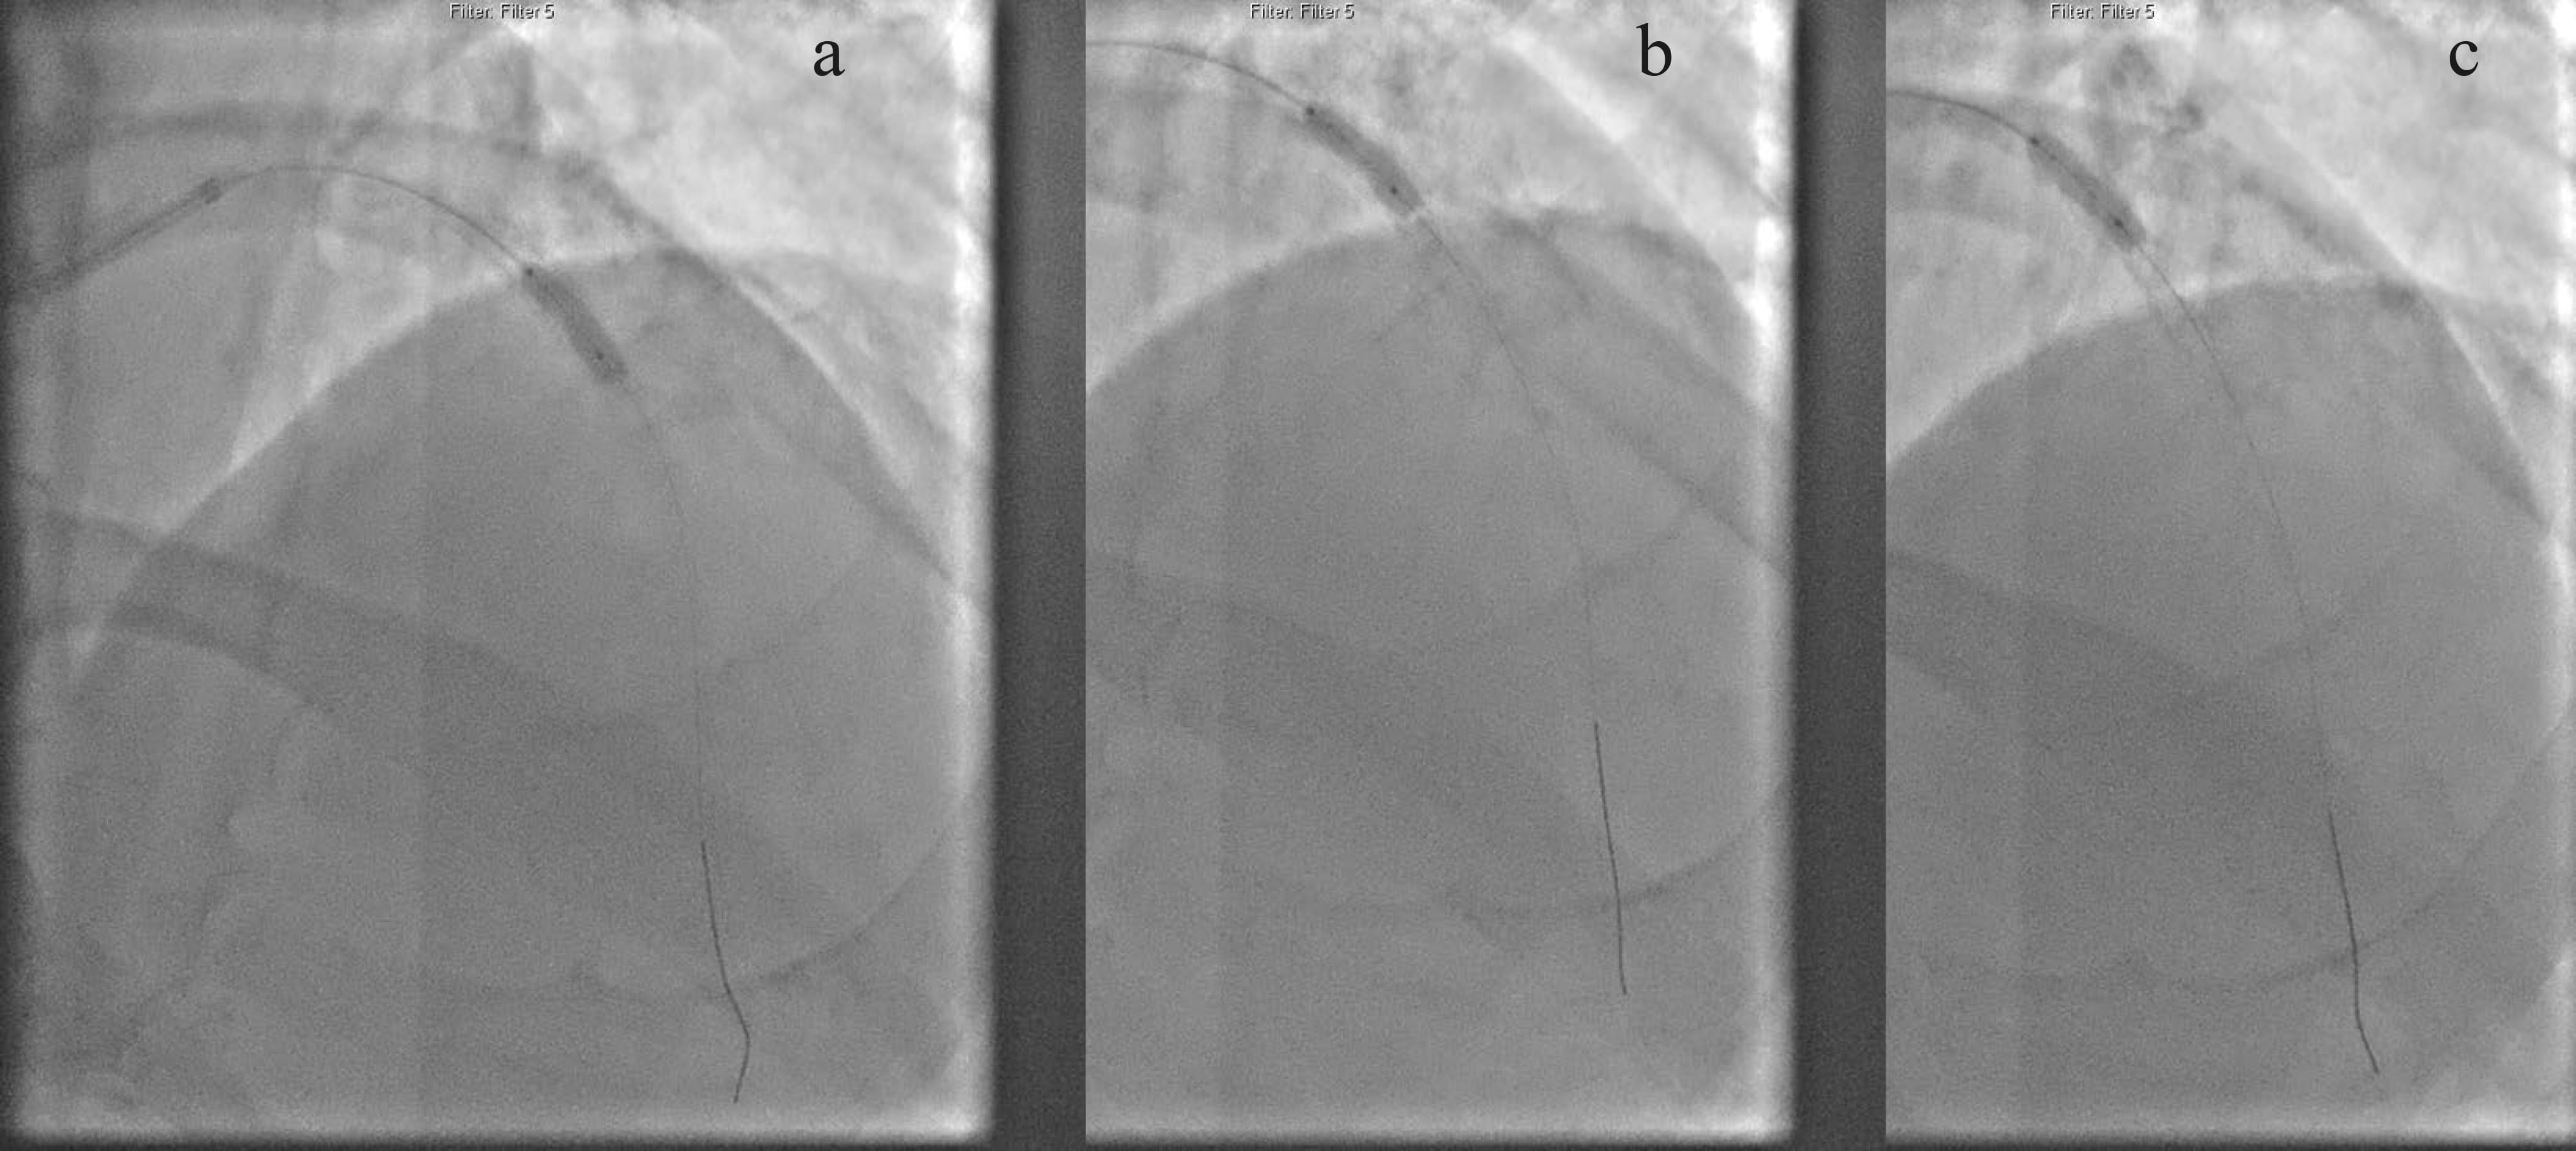

yield with conventional non-compliant balloons (Fig. 2). High pressure inflation

resulted in bursting of a 3.5 mm non-compliant balloon (Fig. 3). Intravascular

Fig. 2.Fluroscopic image showing the inability to prepare the lesions. (a,b) Using non-compliant balloons (2.5 mm and 3.0 mm) at high-pressures giving rise to dog-bone appearance (shown by the arrows). (c) Burst of a 3.5 mm non-compliant balloon when inflated at high-pressure (20 atm) with escape of contrast into the distal LAD and diagonal (shown by the arrows).